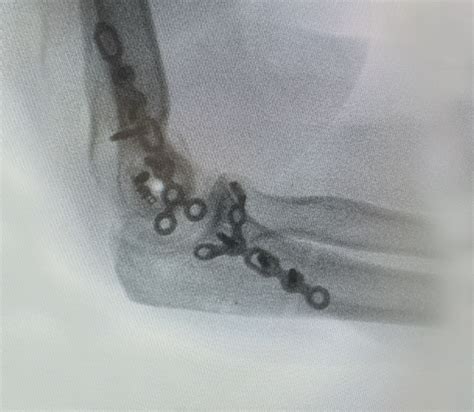

The journey through Open Reduction Internal Fixation Surgery begins with pre-operative preparation, including imaging like X-rays or CT scans. During the procedure, the surgeon follows a systematic approach to ensure safety and precision.

4. Fixation Plates, screws, or intramedullary rods are attached to stabilize the bone.

• Follow-up Imaging: Periodic X-rays are taken to monitor bone union and ensure the hardware remains properly positioned.

Hardware, such as metal plates or screws, is often left inside the body indefinitely. In most cases, these materials are biocompatible and do not cause issues. However, if the hardware becomes uncomfortable or causes localized irritation, surgeons may discuss a secondary, minor surgery to remove it after the bone has fully remodeled.